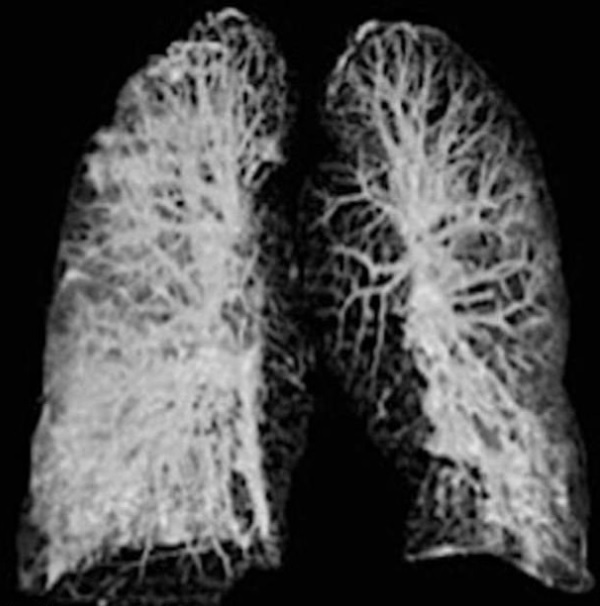

Οι ακτινογραφίες είναι από τον πνεύμονα ενός 60χρονου Κινέζου που βρέθηκε στην Ιταλία.

Στην πρώτη φωτογραφία φαίνεται ο πνεύμονας του την πρώτη μέρα που νόσησε ενώ στη δεύτερη φαίνεται όταν πλέον η κατάσταση έχει προχωρήσει.

Τη δεύτερη σάρωση οι μαλακοί ιστοί των πνευμόνων φαίνονται εξαιρετικά διογκωμένοι.